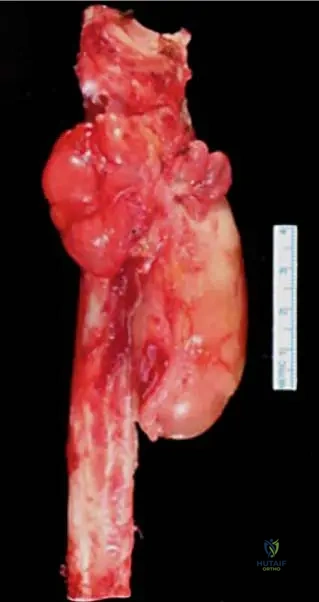

A 59-year-old patient underwent surgical resection of a mass in the lower leg, which included a portion of the proximal fibula due to its close proximity to the tumor. The resected specimen is shown.

Correct Answer: A

Rationale: The clinical context for Fig. 9.18 explicitly states: "Resected proximal fibula with adjacent liposarcoma." Main Distractor: B) Malignant fibrous histiocytoma (MFH). While MFH is a type of soft tissue sarcoma mentioned in the general text, the specific image context identifies the tumor as a liposarcoma.